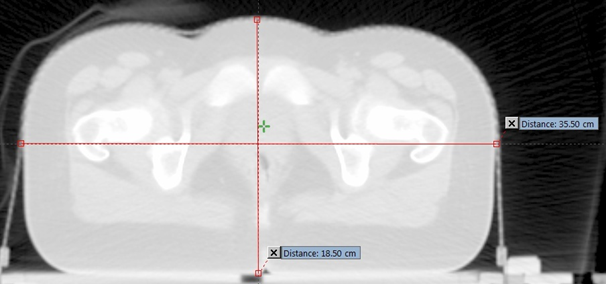

Lateral (LAT) dimension: The lateral dimension is width (left to right dimension) of the body part being scanned. The lateral dimensions of the patient were measured from frontal localizer radiograph as shown in Figure 1. The lateral dimensions were also measured on coronal plane of 3D reconstructed data where maximum dimension occurs to compare its efficacy against localizer radiograph.

Figure 1 Measurement of LAT dimension.